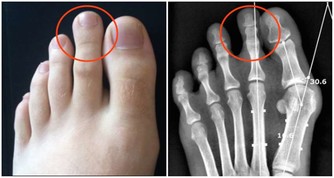

6、高血脂可以預防嗎?

高血脂可以透過生活型態如健康飲食、運動、戒菸等預防或延後發生。雖然有部份高血脂症是家族遺傳,無法預防,但仍需維持健康飲食及運動習慣,避免高血脂症可能提早報到。